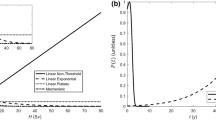

Our study is motivated by radiation therapy design for cancer treatment. We consider large-scale problems with stochastic order constraints. We establish a general result about the form of the deepest cuts associated with events of positive probability which are used in the numerical approximation of the functional constraints. An efficient method using the deepest cuts is proposed for the numerical solution of problems with second-order dominance constraints and increasing convex order constraints. We the propose a new methodology for the radiation-therapy design for cancer treatment. We introduce a risk-averse optimization problem with two types of stochastic order relations and with coherent measures of risk and consider the effect of the risk models in three versions of the problem formulation. Additionally, we propose a method that creates flexible (floating) benchmark distributions when benchmark distributions are not given apriori or when the provided distributions lead to infeasibility. We devise a numerical method using floating benchmarks for solving the proposed risk-averse optimization models for radiation therapy design. The models and methods are verified by using clinical data confirming the viability of the proposed methodology and its efficiency.